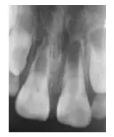

X線片示:11根管短小且粗大,根尖孔未閉合,管壁呈平行狀,根中1/3見內(nèi)吸收,牙根發(fā)育7期,根部未見根折線,根尖周有稀疏區(qū);21根部發(fā)育程度與11相同,根部未見根折線及內(nèi)外吸收,根尖周未見明顯稀疏區(qū)(圖1a)。

圖1a 術前X線片